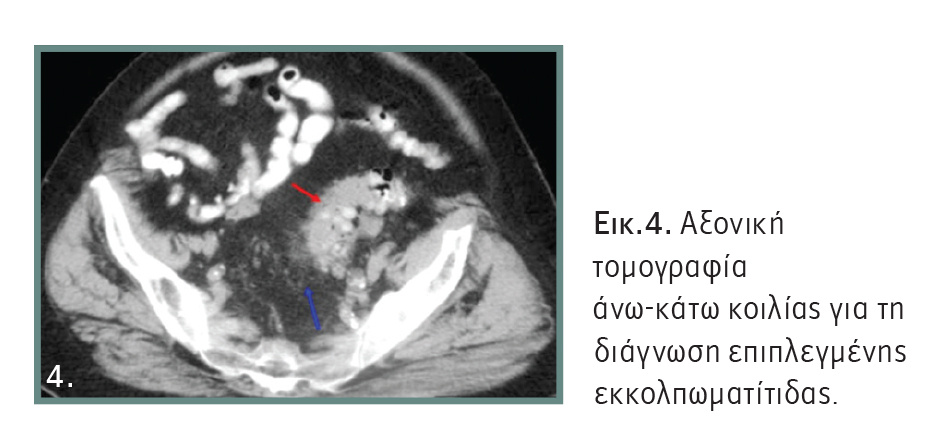

Κλινικά ο ασθενής εμφανίζει σύσπαση στο σημείο της φλεγμονής. Η πρώτη εξέταση που πρέπει να γίνει, είναι ο αιματολογικός έλεγχος, με τον οποίο συνήθως διαπιστώνεται αύξηση των λευκών αιμοσφαιρίων, αλλά και των δεικτών φλεγμονής. Στη συνέχεια, μια καλή υπερηχοτομογραφική μελέτη θα θέσει τη διάγνωση και είναι αρκετή σε απλές περιπτώσεις. Όμως, σε επιπλεγμένη εκκολπωματίτιδα, όπου χρειάζεται νοσηλεία, είναι απαραίτητη η αξονική τομογραφία άνω-κάτω κοιλίας (Εικόνα 4), για να διαπιστωθεί η έκταση της φλεγμονής και ανάλογα να ληφθούν αποφάσεις για την αντιμετώπισή της.